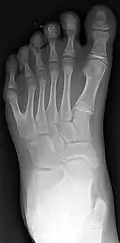

Postaxial polydactyly

This is the most common situation, in which the extra digit is on the ulnar side of the hand, thus the side of the little finger. This can also be called postaxial polydactyly. It can manifest itself very subtly, for instance only as a nubbin on the ulnar side of the little finger, or very distinctly, as a fully developed finger. Most commonly, the extra finger is rudimentary, consisting of an end phalanx with a nail, and connected to the hand with a small skin pedicle. Mostly one neurovascular bundle can be identified, with no tendons present in the extra digit. In case of a fully developed extra finger, the duplication usually presents itself at the level of the metacarpophalangeal joint. A triplication of the little finger is very rare. Ulnar polydactyly occurs ten times more often in African populations.[14] The incidence in Caucasians is reported as 1 in 1,339 live births, compared with 1 in 143 live births in Africans. Ulnar polydactyly is also often part of a syndrome.[14] In patients with African ancestry ulnar polydactyly mostly occurs isolated, whereas the presentation in Caucasians is often associated with a syndrome,[7] though in a retrospective review, only 4 of 37 cases of ulnar polydactyly in Caucasians were syndromic.[15]